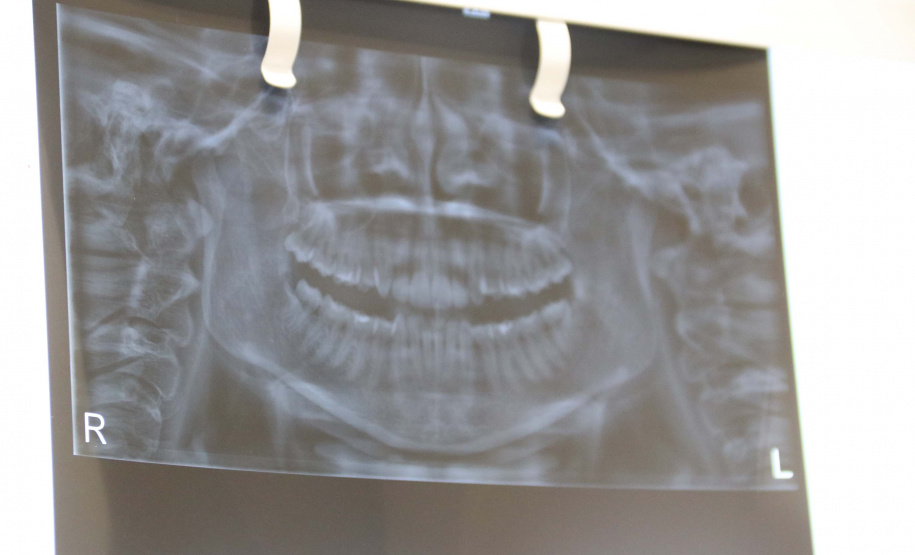

O prontuário odontológico é o conjunto de toda documentação obtida durante o tratamento e mostra uma perspectiva fundamental para os trabalhos dos cirurgiões-dentistas. No IML do Paraná, assim como em várias regiões do País, diversos são os casos de identificação humana possibilitadas por meio de análises das características e especificidades dentais registradas em prontuários.

Os conhecimentos da Odontologia Forense geralmente são adotados para a identificação humana em casos de cadáveres carbonizados, em avançado estado de decomposição, fragmentados e esqueletizados.

“Nesses casos, os profissionais da Polícia Científica chamam os familiares e questionam se a pessoa passou por algum tratamento odontológico. Caso eles tenham conhecimento disso, o dentista da vítima é acionado para que ele possa disponibilizar o prontuário odontológico e, assim, os exames de identificação humana pela arcada dentária possam ser feitos pelos peritos”, explica o diretor da Polícia Científica do Paraná, Luiz Rodrigo Grochocki.

ODONTOLOGIA FORENSE – De acordo com a Polícia Científica, depois da tradicional identificação humana por papiloscopia (impressões digitais), o uso da odontologia forense é a opção mais viável. Além de trazer o resultado rápido, o que agiliza a identificação e liberação do corpo para que a família possa fazer o sepultamento, há menor custo ao Estado do que a identificação por exames de DNA.

“Se for necessário um exame de DNA, a família precisará esperar no mínimo três meses para ter a certeza de que trata-se do corpo de seu familiar. Essa é uma situação que causa muita dor e angústia para quem passa por isso. Além de demorada, a identificação por DNA tem custo muito mais elevado que pela arcada dentária. Por isso, é muito importante que os cirurgiões-dentistas tenham essa documentação preenchida e armazenada corretamente”, completou a perita odontologista.